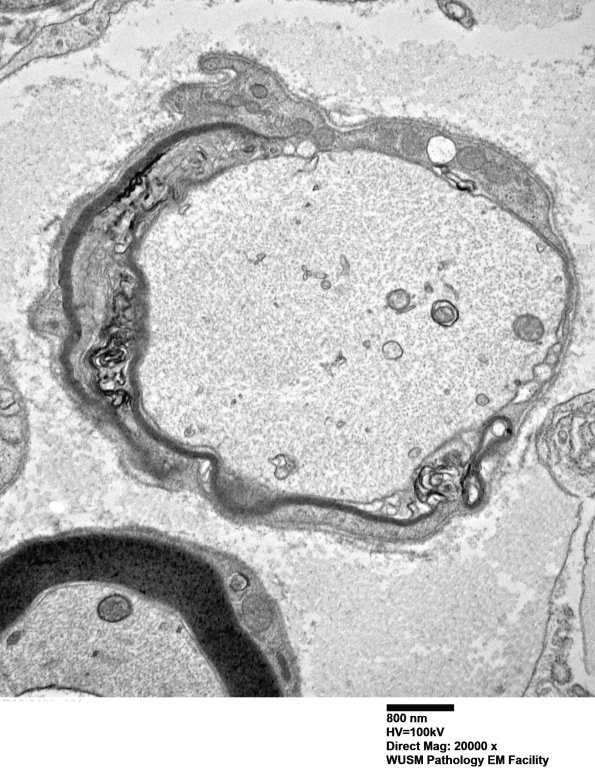

This image shows an early myelination stage in a large axon. (electron micrograph)